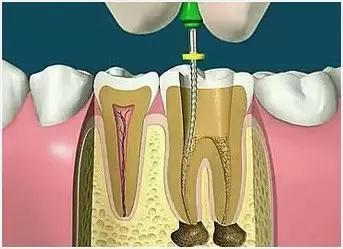

封闭整个根管系统、堵塞主根管和侧副根管出口、防止微生物和液体的渗漏。无论是侧方加压法还是垂直加压法,应做到根管充填致密,根管充填后X光片上无根管腔隙,也不能超出根尖孔。

因牙体缺损过多,导致牙的强度(承受力量的性能)大幅度下降,不能很好地承受咀嚼力量。打桩的目的是增加牙根及牙冠的强度,增加患牙的稳固。

X光片显示根管充填完好,可进行暂时或永久牙体修复,带上牙冠,保护患牙。至此根管治疗才可算完成,同时根管治疗后还需复诊,一般周期可为3个月、半年、1年、2年或更长。